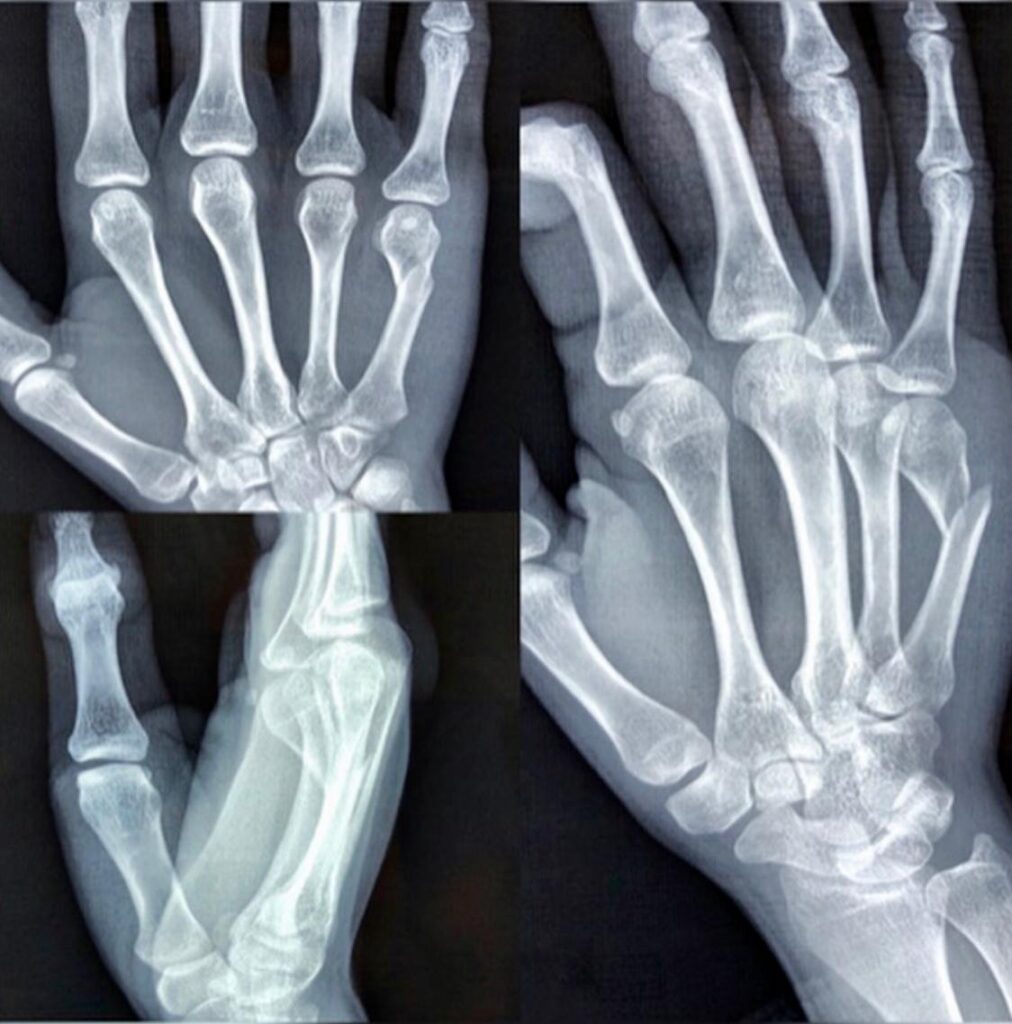

Conocé de forma clara y didáctica cómo explorar y diagnosticar las fracturas, haciendo hincapié en cuáles son las que se deben tratar con cirugía y presentando diversas técnicas de fijación.